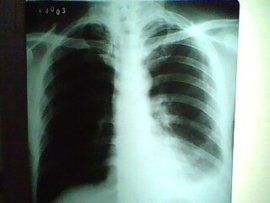

肋膈竇,是人體一個器官名,每側的肋胸膜與膈胸膜在肺下界以下的轉折處稱為肋膈竇。

肋膈竇1.肋膈竇又稱肋膈隱窩。為胸膜壁層的肋部和膈部返折處,左右各一。此竇最大,位置最低,深度一般可達2個肋和肋間隙。胸膜腔積液首先積聚於此。 2.人處於站立...

簡介 心臟的進化 心臟的發育 論文介紹 在肋胸膜與膈胸膜轉折處,形成一個較大的間隙稱為肋膈隱窩或稱肋膈竇,左、右各一 相關條目 肋胸膜 膈胸膜 ...

介紹 相關條目窩(胸膜竇),位於相鄰壁胸膜轉折處。肋胸膜與膈胸膜反折移行處稱肋膈隱窩(肋膈竇),最大,深吸氣時也不能完全被肺充滿,其深度,可因呼吸而有所變化...,尚有很小的膈縱隔隱窩(膈縱隔竇)。胸膜的體表投影前界(肋縱隔反折線...

1、胸膜的解剖結構:移行,在某些部位成隱窩而肺緣並不伸入其間。這些隱窩即胸膜竇。在肋胸膜與膈胸膜的轉折處形成膈肋竇,它是胸膜腔的最低點,胸膜炎時滲出液首先積聚於此...胸膜隱窩(胸膜竇),位於相鄰壁胸膜轉折處。肋胸膜與膈胸膜反折移行處稱肋膈...